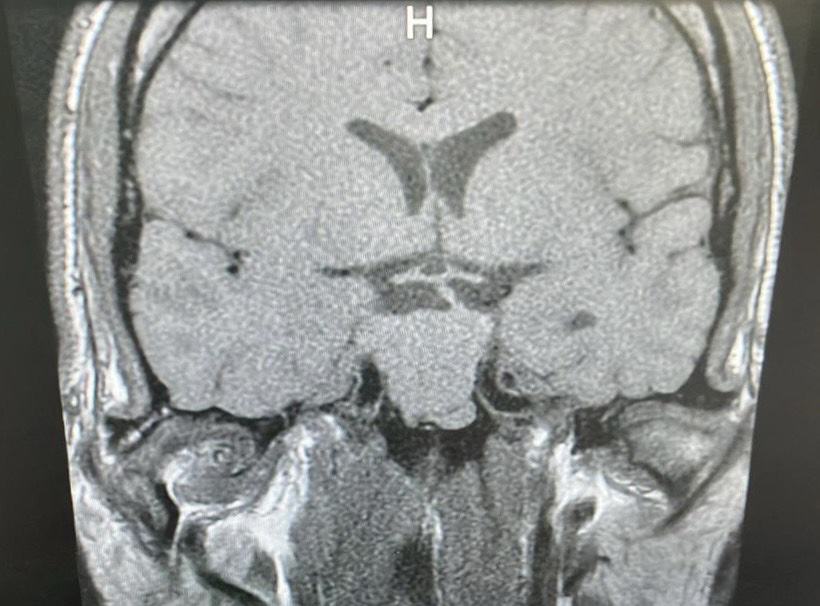

RM de silla turca que revela un tumor selar con extensión al seno esfenoidal y suprasellar con invasión de seno cavernoso bilateral Knosp IV de 28 mm (Figura 1).